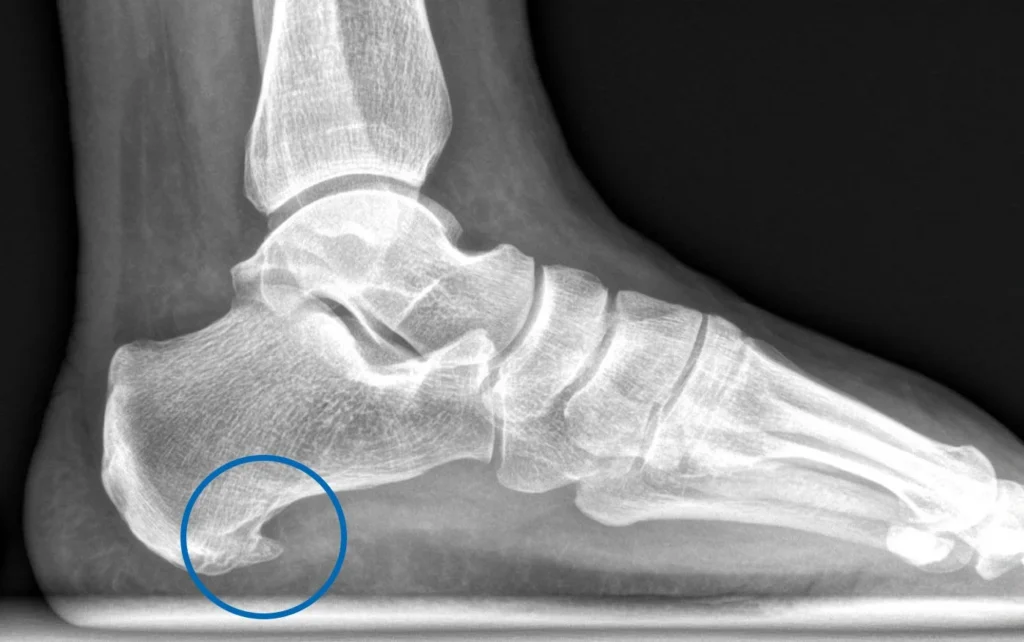

espolón calcáneo Causas, síntomas y tratamiento

El espolón calcáneo es una condición común pero dolorosa que afecta a muchísimas personas. Si el dolor de talón está limitando tu vida, sigue leyendo. En este artículo, te guiaré a través de las causas, los síntomas y, lo más importante, los tratamientos efectivos para que puedas volver a caminar…